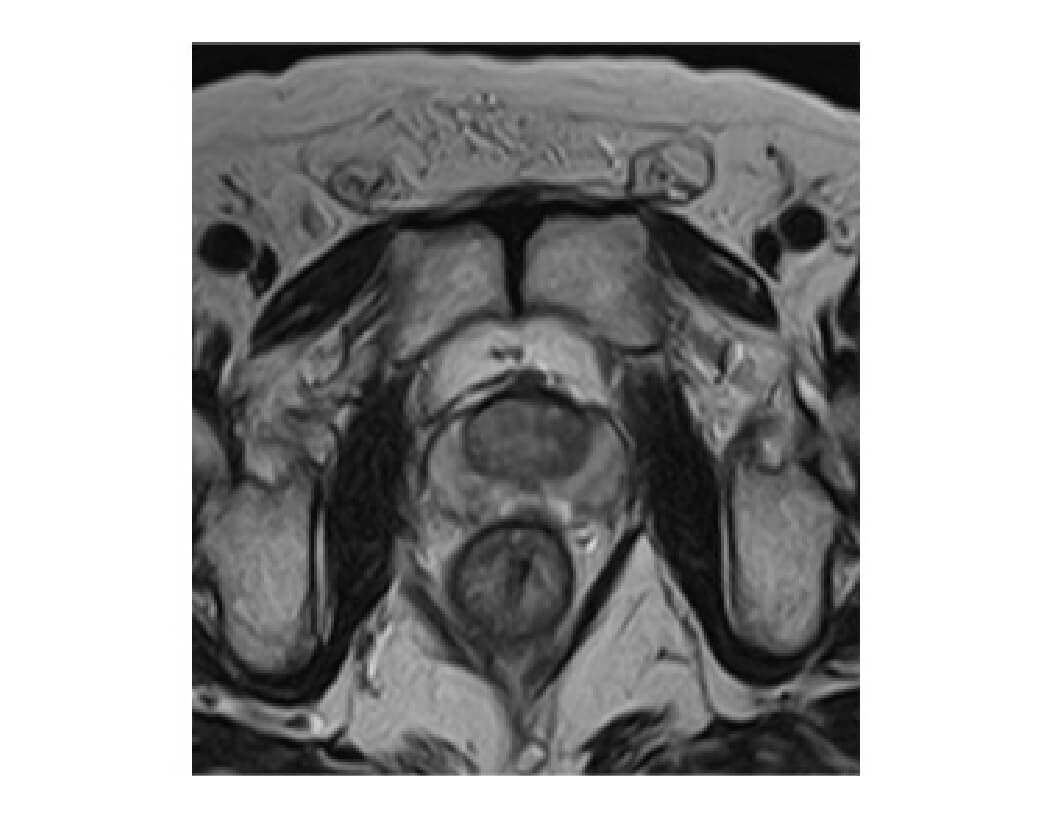

正常な前立腺MRI画像